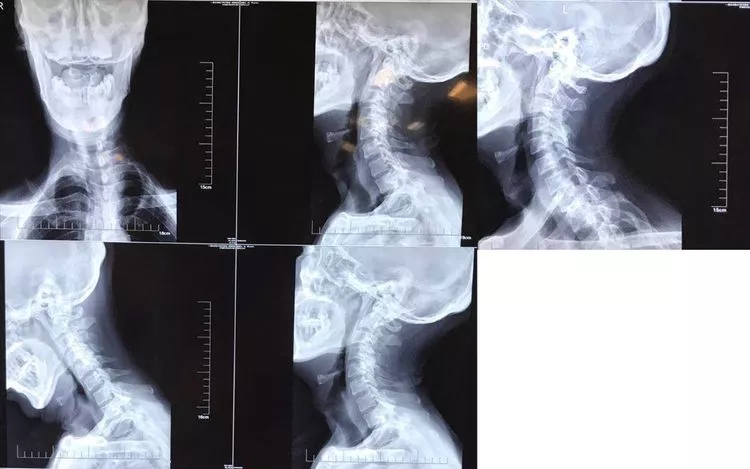

男性,59岁,半年前无诱因出现右半身麻木,伴右侧肢体乏力,右胸壁多汗,行走后右下肢抽痛明显,于当地医院就诊,查颈椎+胸椎+腰椎MRI示“颈髓脊髓空洞,腰4-5椎间盘突出”,对症治疗后症状无明显缓解。现为求进一步诊治,来西安交通大学第一附属医院,门诊以“脊髓空洞”收住入院。

影像学资料

1. Chiairi畸形并颈髓空洞

2. 脊柱侧弯